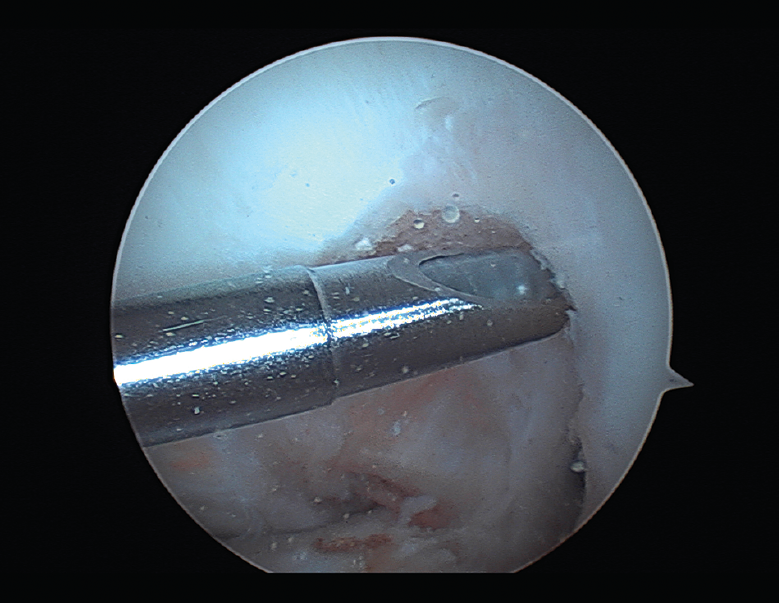

Las principales causas secundarias a errores técnicos son la malposición de la plastia y el tensado excesivo. La radiografía permite ver la localización de los túneles e implantes, así como la RM visualiza las partes blandas implicadas, pudiendo identificar posibles pinzamientos de la plastia –escotadura intercondílea, síndrome del cíclope (Figura 9), síndrome de la contractura infrapatelar(22)(Figura 10)–.

La cronología tras la cirugía es también importante. Durante los 3 primeros meses tras la intervención podemos tratar satisfactoriamente rigideces menores con rehabilitación, antiinflamatorios no esteroideos (AINE) y manipulación. Más allá de los 4 meses, se recomienda desbridamiento artroscópico. No se recomienda la manipulación bajo anestesia sin una liberación articular artroscópica del tejido cicatricial. El desbridamiento artroscópico incluye la retirada de tejido cicatricial, grasa de Hoffa, liberación cuadricipital de la cara anterior femoral y de los recesos laterales, y ocasionalmente liberación de retináculos patelares si la movilidad patelar fuera insuficiente(23).